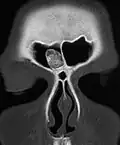

Osteoma represents the most common benign neoplasm of the nose and paranasal sinuses. The cause of osteomas is uncertain, but commonly accepted theories propose embryologic, traumatic, or infectious causes. They are present in Gardner's syndrome.

Larger craniofacial osteomas may cause facial pain, headache, and infection due to obstructed nasofrontal ducts. Often, craniofacial osteoma presents itself through ocular signs and symptoms (such as proptosis).[2]